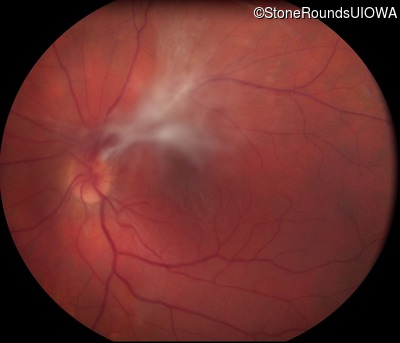

Fundus Photography - Left - 20/20 sc

Exemplar